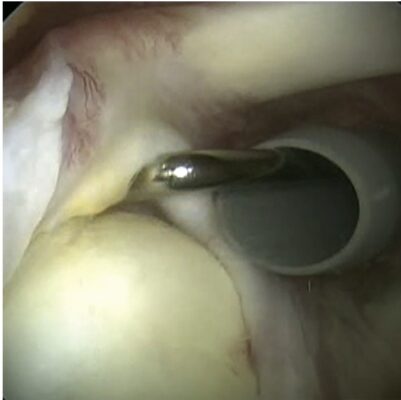

- Nội soi khớp là tiêu chuẩn vàng để chẩn đoán bệnh lý sụn viền. Nhiều khi chẩn đoán được thực hiện trong quá trình nội soi khớp sau khi các phương pháp khác không đưa ra được chẩn đoán chính xác hoặc nếu các triệu chứng vẫn tồn tại dù đã điều trị bảo tồn.

- Loại II: Nội soi khớp sửa chữa bằng khâu neo .

Sửa chữa sụn viền với làm rút lại bao khớp (plication) lỏng có hiệu quả trong việc khôi phục độ ổn định (Hình 6). Với phẫu thuật mổ hở hoặc nội soi khớp, nguy cơ tái phát so với điều trị bảo tồn là khoảng 1/5 so với nhóm không phẫu thuật. Nghiên cứu đã chứng minh rằng phẫu thuật mổ hở và nội soi khớp để điều trị mất vững khớp vai tái phát có kết quả như nhau khi theo dõi 2 năm. Tuy nhiên, tỷ lệ tái phát cao hơn một chút khi điều trị nội soi khớp, có thể là do ít hình thành mô sẹo